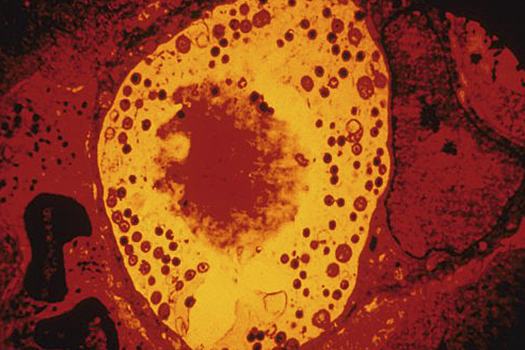

Анализ показал, что у пациентов с болезнью Альцгеймера в тканях сетчатки и головного мозга обнаруживались значительно более высокие концентрации хламидий. Это род грамотрицательных бактерий, виды которых относятся к облигатным внутриклеточным паразитам. Хламидии вызывают заболевания у человека, животных и птиц.